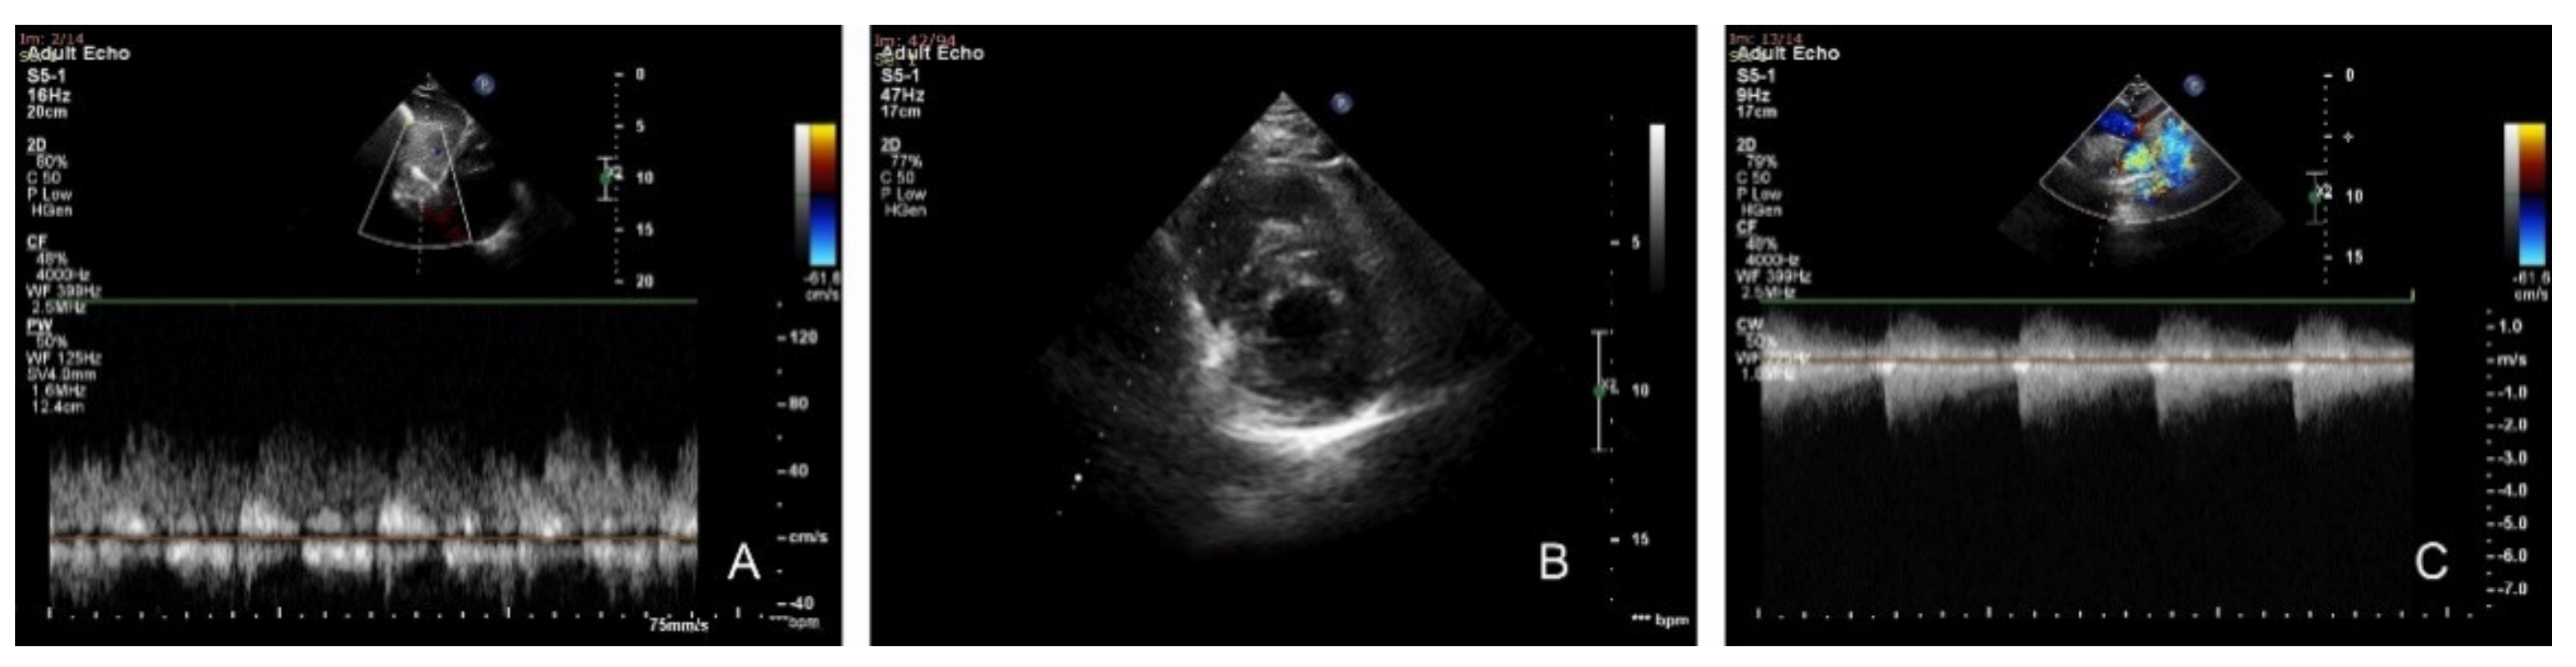

Follow Up at 1 Month